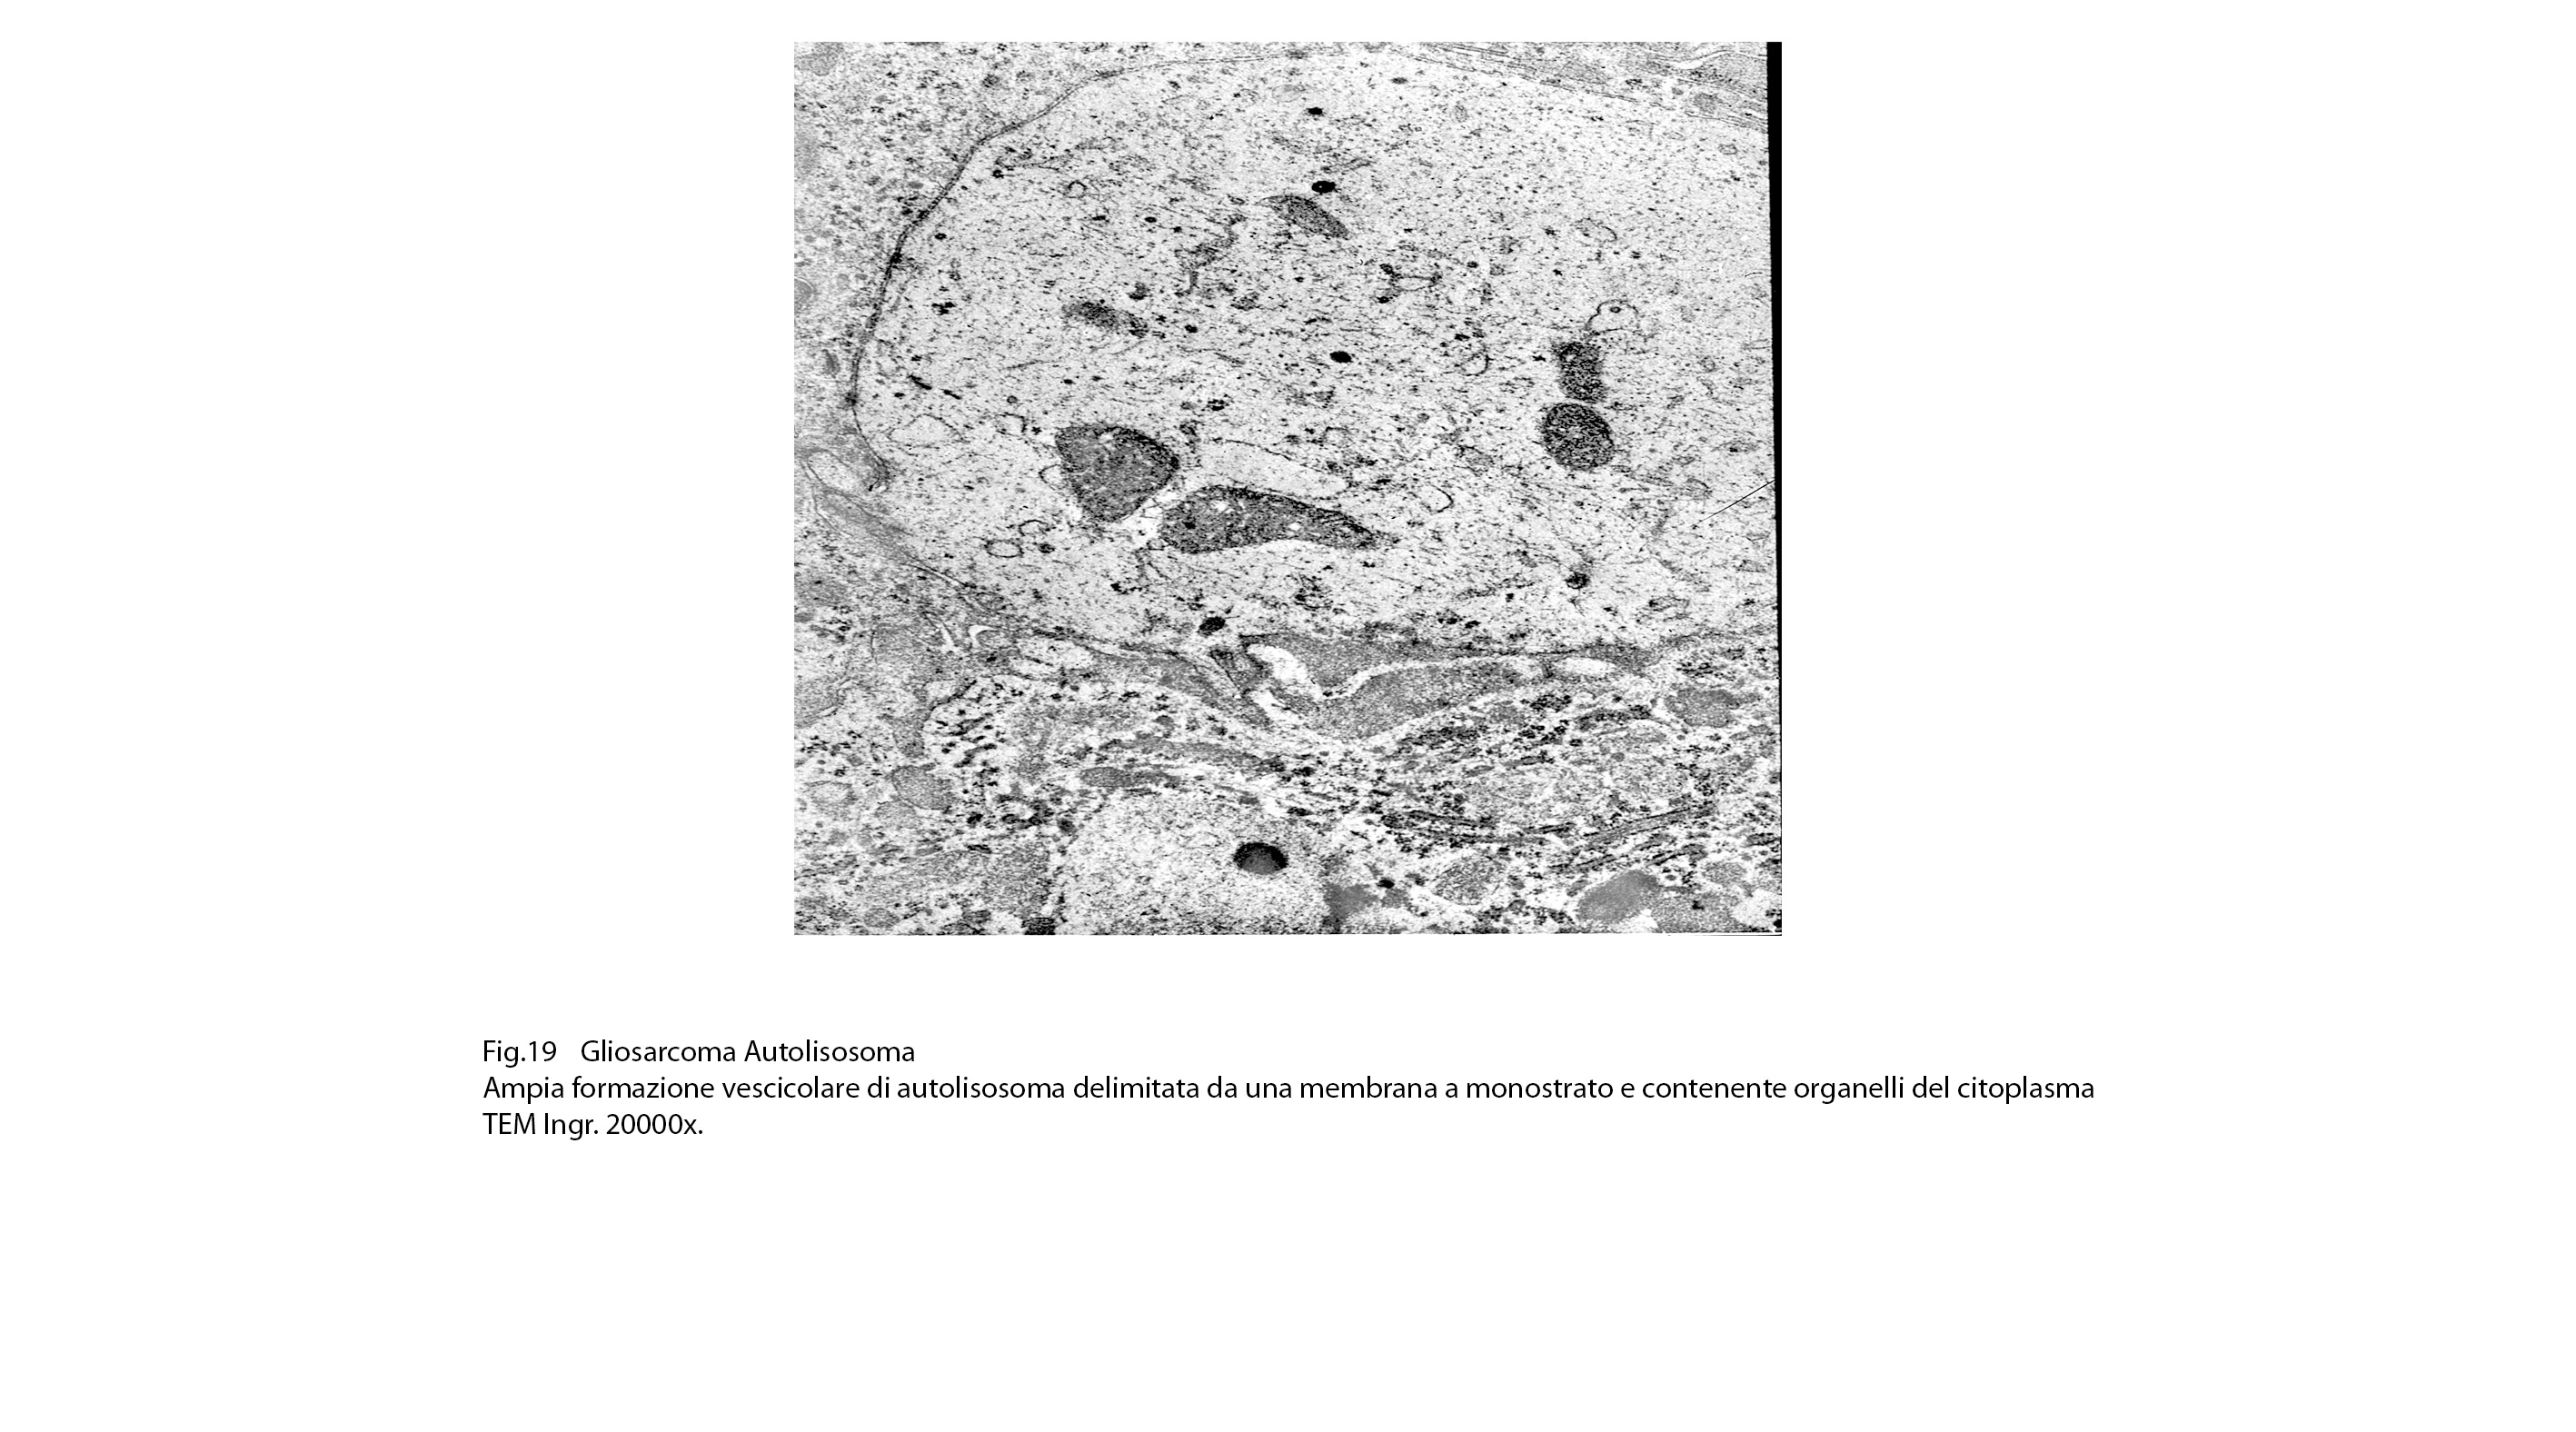

Dopo questa fase di accumulo del cargo,segue quella della fusione tra l’autofagosoma e un lisosoma con formazione di una nuova struttura indicata con il termine di autolisosoma.

Gli autolisosomi inizialmente mostrano una doppia membrana di contorno,successivamente la membrana interna viene demolita dagli enzimi lisosomiali e appaiono come sub strutture vescicolose delimitate da una membrana a monostrato; pertanto si distinguono con difficoltà dai lisosomi secondari.(Margit Pavelka, Jurgen Roth: Functional Ultrastructure,Springer Verlag, 2015).

Nel citoplasma delle cellule di gliosarcoma esaminate sono stati riscontrati con frequenza focolai di autofagosomi e di autolisosomi; i primi si riconoscono quali corpi ovoidali o rotondeggianti i quali sono demarcati da una membrana a doppio contorno e contengono nel loro spazio cavo materiale granuloso,filamentoso ed amorfo; i secondi,gli autolisosomi, sono delimitati da una membrana a monostrato,spesso notevolmente ispessita per sovrapposizione di materiale amorfo;il loro contenuto è rappresentato da materiale biologico in varie fasi di degradazione.

Fig.18  Fig.19

Fig.19